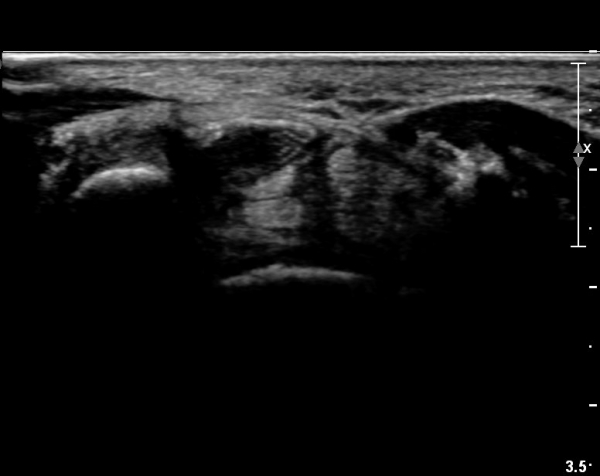

ÀÌ·± ¸ð½ÀÀº ¼Õ¸ñÀÇ ¿ù»ó°ñ ºÎÀ§(»çÁø 3, 4)¸¦ Áö³ª ¼ö±Ù°ü ±ÙÀ§ºÎ ±îÁö À̾îÁü(»çÁø 5).

ÇÏŰ½ºÆ½(°íÁÖÆÄ) ŽÃËÀÚ¸¦·Î °üÂûµÈ ¸ð½À¿¡¼­ Á¤Áß½Å°æ ºÎºÐ ½Å°æ´Ù¹ßÀÇ Àú¿¡ÄÚ

º¯È­°¡ ¶Ñ·ÈÇÔ(»çÁø 6, 7).

Á¤Á߽Űæ Á¾´Ü¸é°Ë»ç¿¡¼­µµ ¼Õ¸ñ ¸»´ÜºÎ¿¡¼­ ¼ö±Ù°ü ±ÙÀ§ºÎ±îÁö À̾îÁø Àú¿¡ÄÚ

Á¾¾çÀÌ °üÂûµÊ(»çÁø 8, 9, 10, 11).